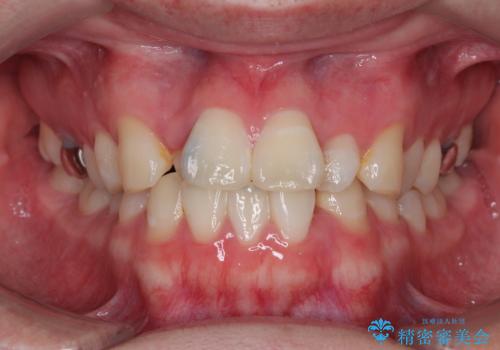

- 30代男性

- 上下顎歯列のデコボコを改善したいとのことで来院された患者様です。

自己管理の大変なインビザラインや、目立つ表側のワイヤー矯正は避けたいとのことで、

上顎だけ裏側装置のハーフリンガルにて矯正しました。